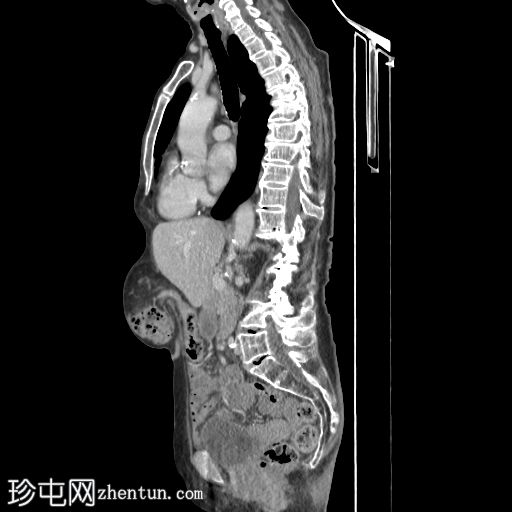

矢状位增强扫描(门静脉期)

6.jpg

三个月后,患者因急性腹痛伴呕吐就诊。

影像表现为小肠梗阻,移行区位于右侧闭孔疝处。疝囊内有少量积液,提示缺血性改变。

无气腹。